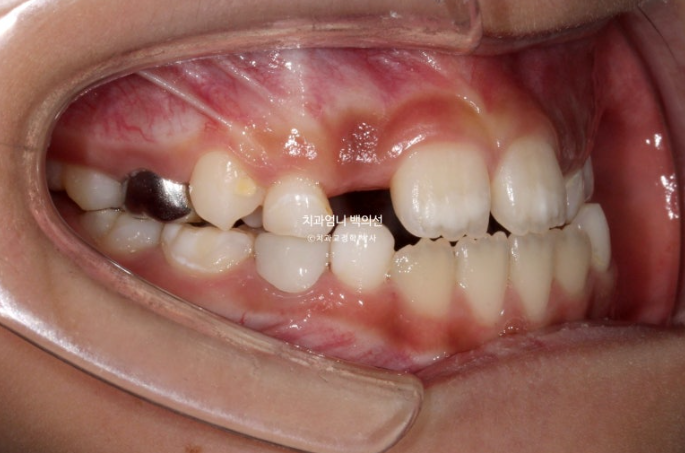

윗니가 아랫니를 덮지 못하는 절단교합입니다.

측절치와 송곳니날 자리가 부족해서 악궁확장도 필요한 상황입니다.

인비절라인 퍼스트로 치료에 들어갔고 악궁확장으로 영구치 맹출공간 회복, 공간 분배, 반대교합 해소로 교합간섭 해소에 의한 아래턱 위치 개선으로 비대칭 해결 등을 목표로 치료에 들어갔습니다.

악궁확장으로 파란 화살표 반대교합이 해소가 되면서 교합간섭이 사라졌습니다.

아래 붙어있는 메탈 고리는 고무줄 거는 고리입니다.

악궁확장으로 넓어진 악궁 덕분에 공간이 좁아 못 나오던 측절치도 잘 나오고 있습니다.